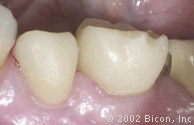

37. | 就位的一体化基台冠的颊侧观,可以注意到双尖牙与对颌牙无咬合关系。 |